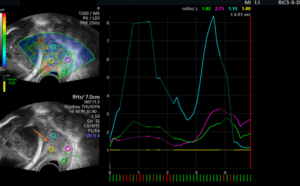

Cervical elastography is an advanced ultrasound technique that evaluates the stiffness (elasticity) of the cervix. Unlike a routine ultrasound, elastography provides quantitative information about cervical tissue, helping doctors assess conditions related to pregnancy, infertility, and cervical disorders with greater precision.

Traditionally, assessing the cervix relied on manual examination or standard ultrasound, both of which provide limited information. Elastography adds a functional dimension — it helps clinicians “see beyond” structure and understand how the cervix behaves under pressure, allowing for: